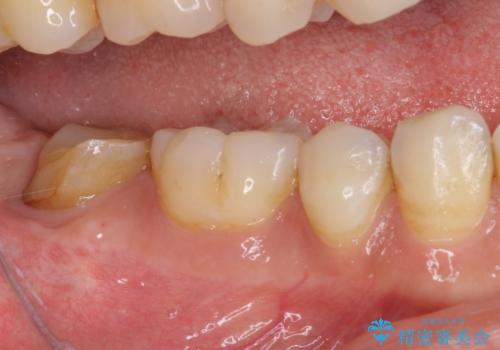

- 根管治療の専門医院で根管治療を行った後、セラミッククラウンによる補綴治療を希望して来院された患者様です。

根管治療後の土台も構築されていたので、仮歯に置き換えた後にフルジルコニアクラウンにて補綴することとしました。

遠心の歯肉が盛り上がっていたため、清掃性が悪くなる懸念がありましたが、クラウン装着による歯肉の腫れは認められませんでした。